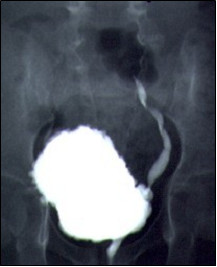

U 2-letniej dziewczynki z nawracającymi zakażeniami układu moczowego, wykonano cystografię, której obraz jest pokazany poniżej. Jakie postępowanie powinno być wdrożone?

Dziewczynka 1-miesięczna po operacji przepukliny oponowo-rdzeniowej z zakażeniem układu moczowego, została przyjęta do oddziału pediatrycznego. Po wyleczeniu zakażenia stwierdzono podwyższenie poziomu kreatyniny do 1 mg%, w badaniu USG poszerzenie układów kielichowo-miedniczkowych i moczowodów. Badanie urodynamiczne wykazało zmniejszoną podatność pęcherza z ciśnieniem powyżej 160 cm H2O pod koniec wypełniania. Wynik cystografii mikcyjnej na załączonym obrazie. Najbardziej optymalnym sposobem leczenia będzie: